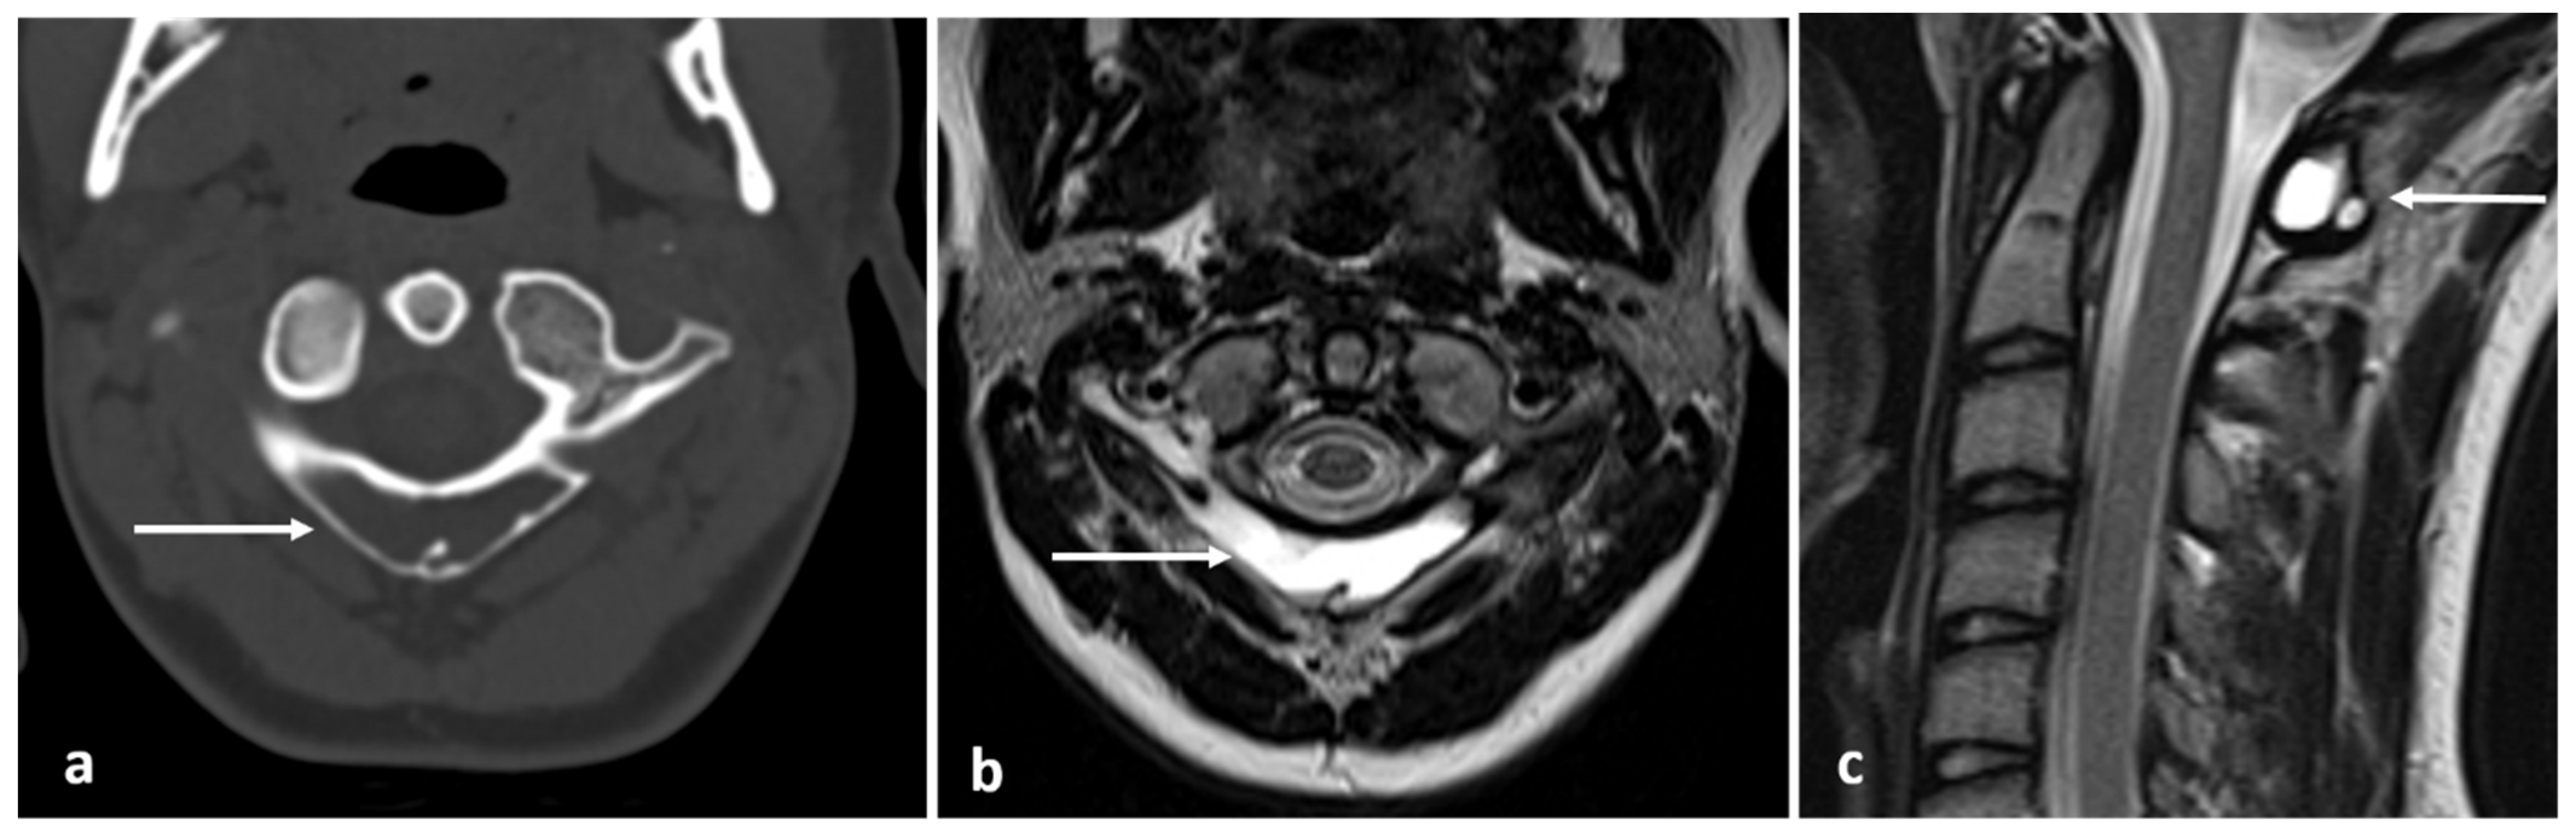

| Aneurysmal bone cyst | Expansile lytic lesion with internal bone septations. | Fluid—fluid levels within the cysts, high T1 signal within layering fluid content due to haemorrhage. |